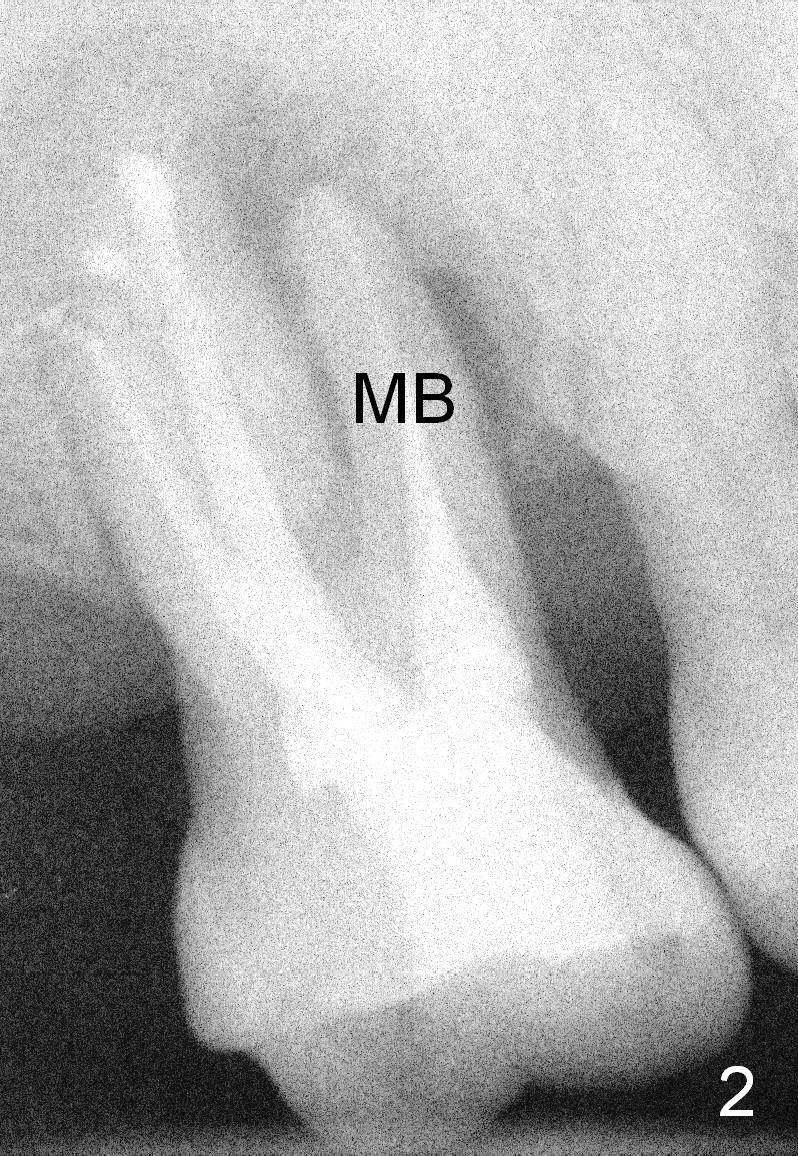

Two years post RCT, there is radiolucency around the MB root of the tooth #3 (Fig.1,2). Eleven days later, there is acute infection associated with MB and DB root fracture (Fig.3). According to the X-ray taken 11 days earlier (Fig.1,4), a long tissue-level implant (6x17 mm) is suitable for the site. In accordance with CBCT (coronal (Fig.5) and sagittal (Fig.6) sections) taken prior to RCT, a short bone-level implant (6.9x10 mm) is a more reasonable choice.